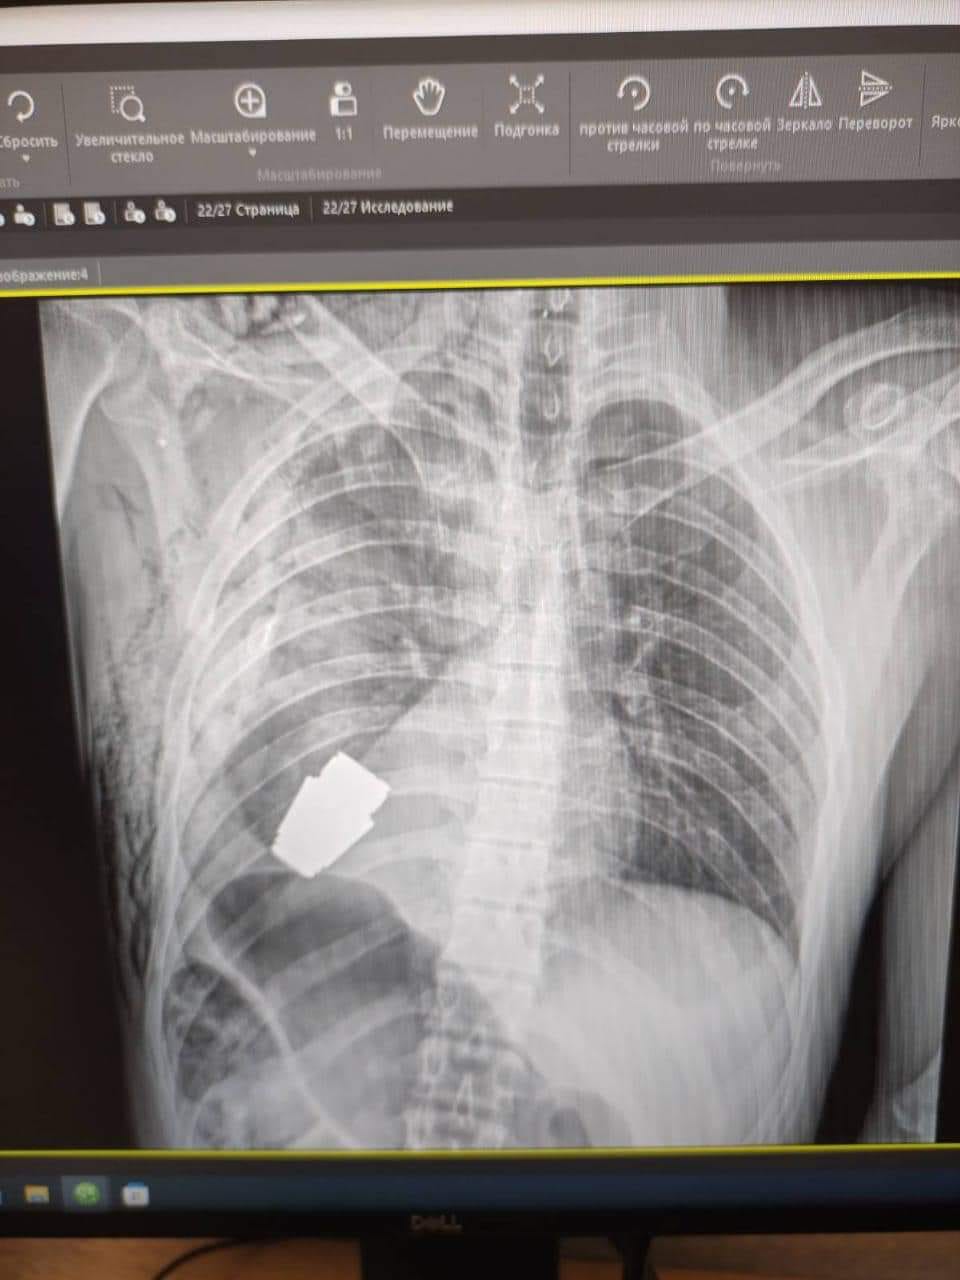

Один з найдосвідченіших хірургів ЗСУ, генерал-майор Андрій Верба, працював без електрокоагуляції, оскільки граната могла детонувати у будь-який момент.